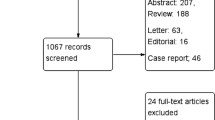

FDG PET/CT images of 60 patients were evaluated, 30 having biopsy-proven giant cell arteritis (GCA; the most common form of large-artery vasculitis), and 30 with severe atherosclerosis. Images were evaluated by 12 nuclear medicine physicians using 5 criteria: FDG uptake pattern (intensity, distribution, circularity), the degree of calcification, and co-localization of calcifications with FDG-uptake. Criteria that passed agreement, and reliability tests were subsequently analysed for accuracy using receiver operator curve (ROC) analyses. Criteria that showed discriminative ability were then combined in a multi-component scoring system. Both initial and final ‘gestalt’ conclusion were also reported by observers before and after detailed examination of the images.

Participants were recruited both retrospectively and prospectively from 6 participating centres. The protocol was approved by the Medical Ethics Committees of involved hospitals.

The vasculitis group contained patients 50 years and older, who were initially diagnosed with probable large-artery vasculitis based on FDG PET/CT results, which diagnosis was subsequently confirmed by temporal artery biopsy. The age limit was waived in one case to include a patient of 47 years who met all other criteria for GCA. To ensure that the GCA group would be representative of daily clinical practice, absence of atherosclerosis was not a criterion for the GCA group.

Atherosclerosis patients were recruited prospectively from a database of vascular outpatients having recently (< 2 years) undergone CT angiography for identification of possible indications for vascular reconstructive surgery. Thus, all patients in this group had severe atherosclerosis in multiple vessels, as assessed by board certified vascular surgeons. After informed consent, these patients underwent additional FDG PET/CT for inclusion in the current study.

Exclusion criteria for both groups included the use of immunosuppressive drugs (corticosteroids or any other immunosuppressor), a diagnosis of cancer and reluctance or inability to provide informed consent. Several additional exclusion criteria applied to the atherosclerosis group to prevent accidental inclusion of patients with undiagnosed vasculitis: erythrocyte sedimentation rate (ESR) > 30 mmHg, C-reactive protein (CRP) > 10 mg/l, myalgia in shoulder/pelvic regions (suggesting polymyalgia rheumatica) and any history of vasculitis or systemic autoimmune disease.